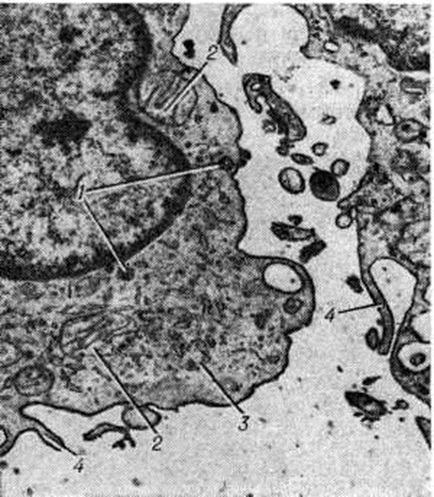

Рис. 3.

Электронограмма синовиоцитов типа А синовиальной оболочки сустава при ревматоидном артрите: гиперплазия лизосом (1), митохондрий (2), зернистой эндоплазматической сети (3) и филоподий (4); ×600.

В гистологический картине синовита выделяют следующие изменения: 1) поражение сосудов микроциркуляторного русла; 2) гиперплазию и гипертрофию синовиальных клеток; 3) воспалительную клеточную инфильтрацию; 4) разрастание грануляционной ткани, склероз, липоматоз синовиальной собственной пластинки. Повышается проницаемость стенок сосудов микроциркуляторного русла, сопровождающаяся выходом фибринозного экссудата и образованием очагов фибриноида в синовиальной собственной пластинке и фибриноподобных наложений на поверхности синовиальной оболочки. Иммуноморфологически в очагах фибриноида и в фибриноподобных наложениях выявляются фибрин, иммуноглобулины (G, А, М) и С3-фракция комплемента. При обострении воспаления постоянно отмечается продуктивный или продуктивно-деструктивный васкулит с фиксацией в сосудистой стенке иммуноглобулинов и комплемента. В глубоких слоях синовиальной оболочки (смотри полный свод знаний) изредка определяются ревматоидные узелки — небольшие участки фибриноидного некроза, окружённые макрофагами и лимфоцитами. В 80% случаев встречается гиперплазия и гипертрофия синовиоцитов с характерным палисадообразным их расположением (рисунок 2). С помощью электронно-микроскопического исследования обнаружено, что гипертрофия синовиоцитов происходит за счёт гиперплазии их органелл, особенно зернистой эндоплазматической сети, полисом, аппарата Гольджи и лизосом (рисунок 3). В гиперплазии ворсинчатого слоя синовиальной оболочки участвуют синовиоциты всех трёх типов (А, В и С). На ранних стадиях обострения воспаления клеточная инфильтрация в синовиальной оболочке скудная, представлена лимфоцитами, макрофагами и полиморфно-ядерными лейкоцитами. В дальнейшем отмечается лимфоидно-плазмоцитарная инфильтрация (рисунок 4), иногда с формированием лимфоидных фолликулов. Параллельно при иммунофлюоресцентном изучении Т и В-лимфоцитов синовиальной оболочки при Ревматоидный артрит Банкхерст (A. D. Bankhurst) с соавторами (1976) выявил преобладание Т-лимфоцитов. В синовиальной оболочке отмечается значительная пролиферация фибробластов. В синовиальной собственной пластинке и фиброзном слое наблюдается разрастание грануляционной ткани с исходом в склероз (смотри полный свод знаний) и липоматоз (смотри полный свод знаний).